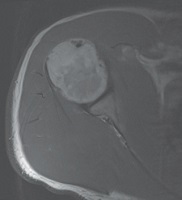

• Upper Arm by MAJOR / Musculoskeletal Anatomy